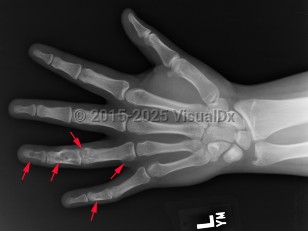

Ollier disease and Maffucci syndrome are nonhereditary conditions that present as multiple enchondromas. Ollier disease involves multiple asymmetric enchondromas of the digits. It is most commonly seen in childhood. These slow-growing tumors usually stop growing after puberty, but masses can create deformity and limb asymmetry. Pathologic fractures may be seen. Ollier disease has a 15%-20% risk for secondary chondrosarcoma.

Classic history and presentation: The proximal phalanx is the typical location. These tumors are also common incidental findings in the distal femur, proximal humerus, and tibia. Mean length is usually less than 5 cm.

Pathophysiology: Enchondroma pathophysiology is believed to involve incomplete endochondral ossification in which physeal remnants become entrapped in the medullary cavity of the metaphysis and proliferate. In the hand, enchondromas are typically diagnosed after a pathologic fracture. Elsewhere, they are typically an asymptomatic incidental finding on x-ray or advanced imaging performed for other reasons. Pain is usually due to a nearby abnormality rather than the tumor itself.